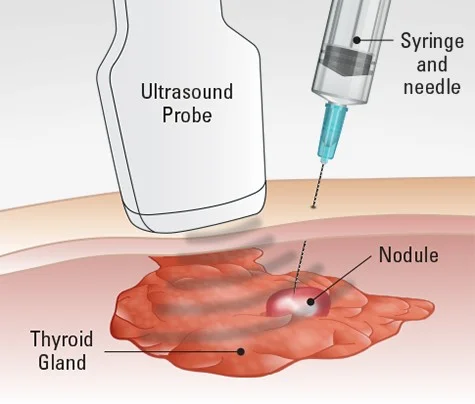

- بیوپسی سوزنی (Needle biopsy): بیوپسی سوزنی نسبت به بیوپسیهای برشی یا اکسیزیونال تهاجم کمتری دارد زیرا هیچ برشی در پوست وجود ندارد اما اشکال این است که ممکن است بافت کافی برای تشخیص HL (یا پیدا کردن نوع آن) نداشته باشد. 2 نوع اصلی بیوپسی سوزنی وجود دارد:

- بیوپسی با سوزن ظریف (fine needle aspiration یا FNA) از یک سوزن بسیار نازک و توخالی متصل به سرنگ استفاده میکند تا مقدار کمی مایع و تکههای ریز بافت را خارج کند.

بیوپسی با سوزن مرکزی (core needle biopsy) از یک سوزن بزرگتر برای برداشتن یک قطعه کمی بزرگتر از بافت استفاده میکند.

برای بیوپسی یک گره بزرگ شده درست زیر پوست، پزشک میتواند سوزن را در حالی که گره را احساس میکند، نشانه بگیرد. اگر یک گره یا تومور در اعماق بدن باشد، میتوان از سی تی اسکن یا اولتراسوند برای هدایت سوزن استفاده کرد.

اکثر پزشکان از بیوپسی سوزنی (به ویژه بیوپسی FNA) برای تشخیص HL استفاده نمیکنند اما اگر پزشک مشکوک باشد که تورم غدد لنفاوی ناشی از عفونت یا گسترش سرطان از اندام دیگری (مانند سینه، ریه یا تیروئید) است، بیوپسی سوزنی ممکن است اولین نوع بیوپسی باشد. حتی پس از انجام بیوپسی سوزنی ممکن است همچنان برای تشخیص HL نیاز به بیوپسی اکسیزیونال باشد.

اگر HL قبلاً تشخیص داده شده باشد، گاهی اوقات از بیوپسی سوزنی برای بررسی تغییرات (مانند گرههای متورم) در سایر قسمتهای بدن که ممکن است ناشی از گسترش یا بازگشت لنفوم پس از درمان باشد، استفاده میشود.